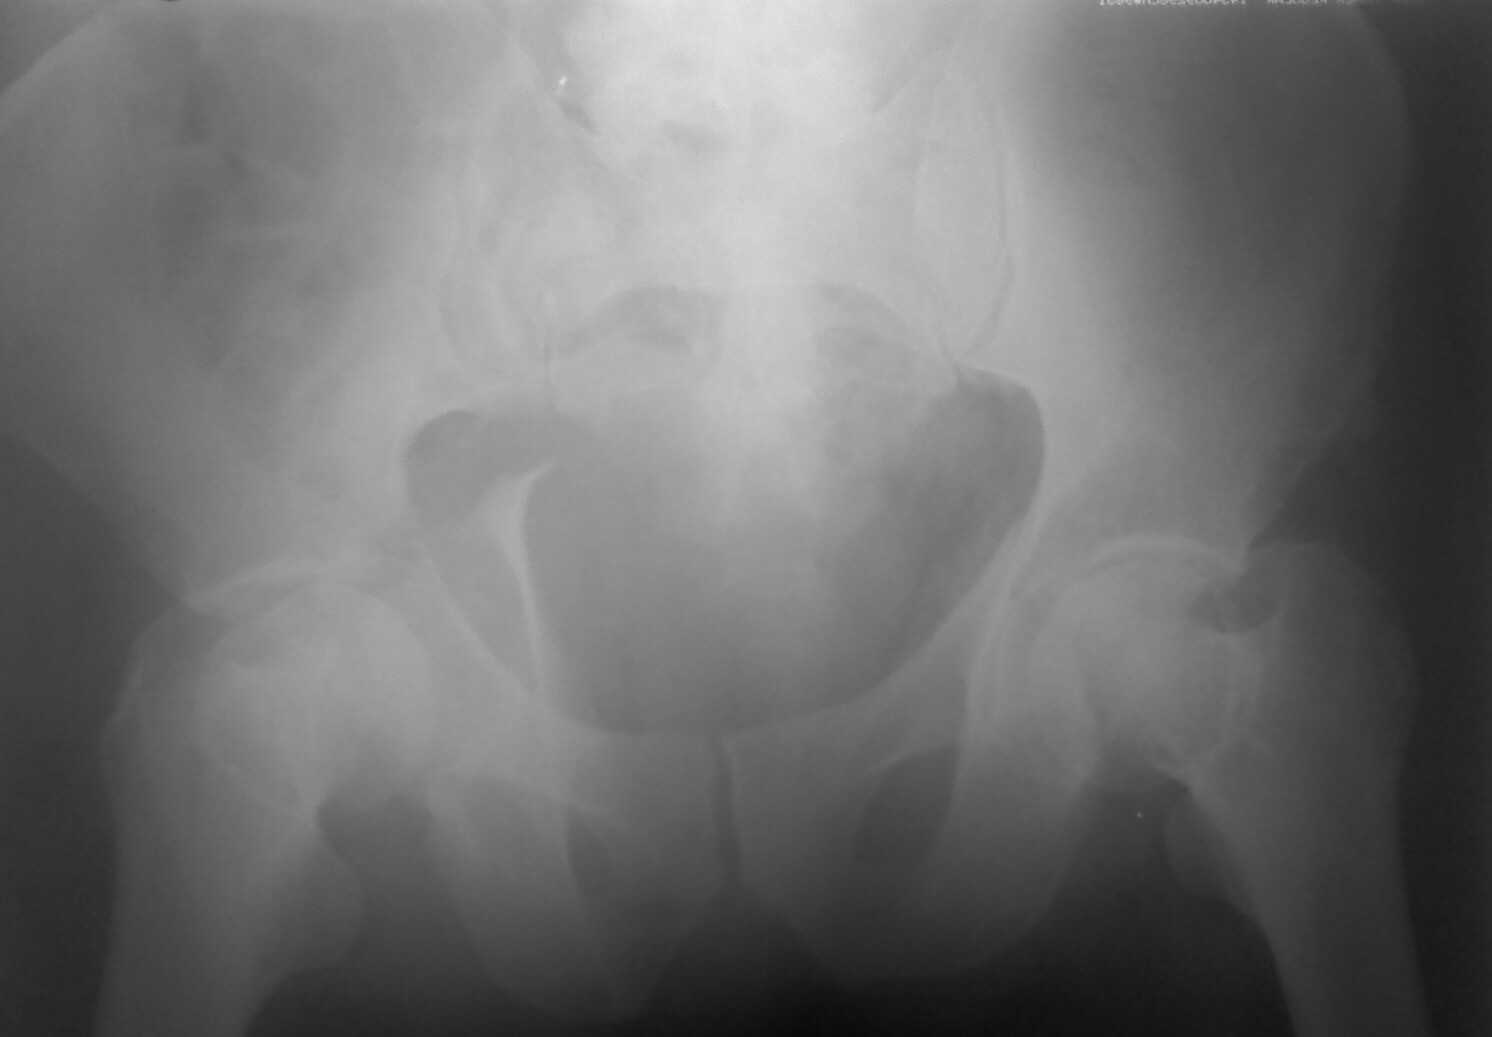

Re: Перелом вертлужных впадин

послал Миронов Андрей 26 Апрель 2008, 22:41

Извините, пробую еще раз